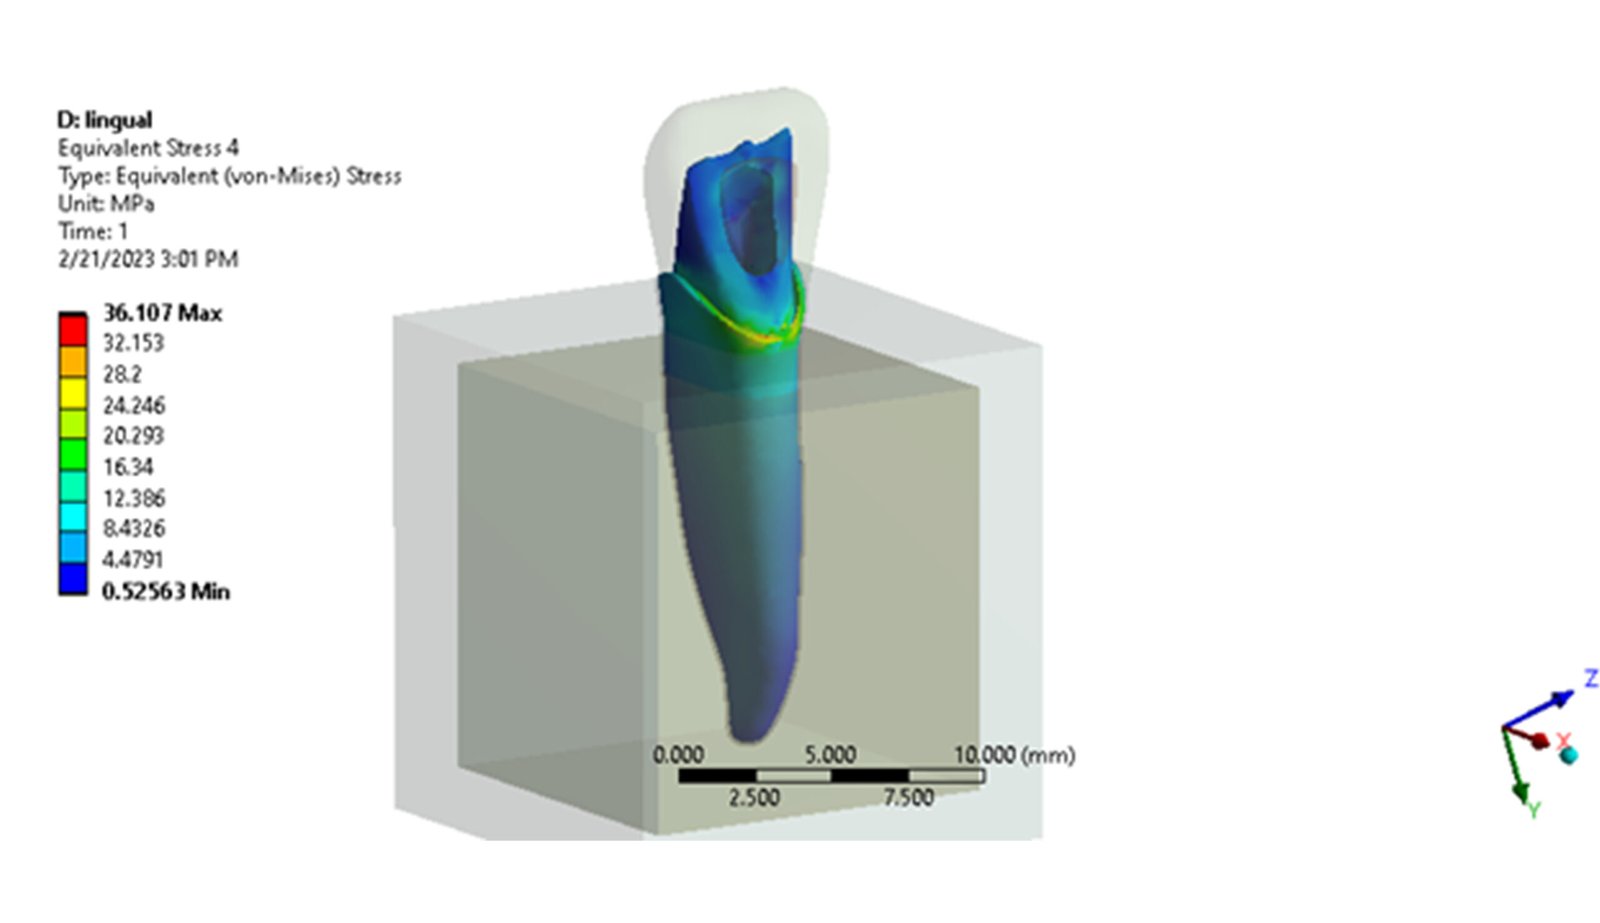

The Endodontic FEA section evaluates the biomechanical performance of root canal–treated teeth, endodontic tools, and reinforcement strategies. Through precise material characterization and micro-CT–based superimposition, we assess fracture risk, stress pathways, and instrument fatigue under various clinical scenarios. These simulations guide the selection of safer instrumentation techniques and restorative strategies. Our goal is to enhance predictability and reduce procedural complications.